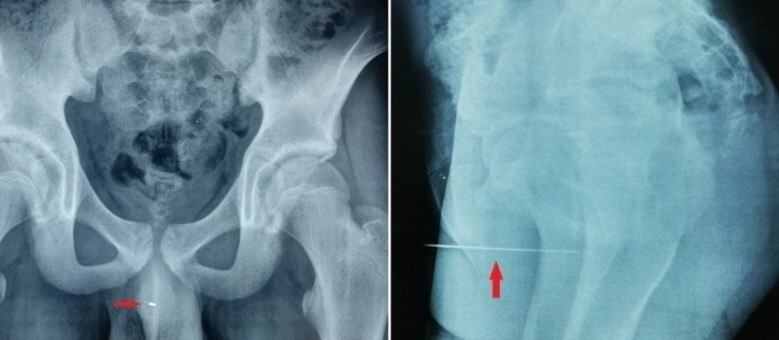

Não era possível ver o objeto, que estava a cerca de 5 cm dentro da uretra. Uma radiografia mostrou a localização exata da agulha.